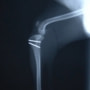

■ 症例22 ポメラニアン 1歳5か月 去勢雄

左後肢の挙上を主訴に来院した。整形学的検査、レントゲン検査より左右の膝蓋骨脱臼(左GradeⅡ〜Ⅲ、右Grade Ⅱ)を認めた。また、脛骨の前方引き出し試験の際に、引き出し兆候は認められないものの、疼痛が認められたため、前十字靭帯の損傷が疑われた。術中における、目視および関節内の操作によって、前十字靭帯の損傷や過伸展といった異常が認められなかったため、膝蓋骨脱臼の整復のみ実施した。手術手技は縫工筋及び内側広筋の解放、脛骨粗面の外側転位、滑車ブロック形造溝術、内外側関節包の縫縮を実施した。本症例は跛行もなく経過良好である。しかし、頸骨高平部の角度(TPA)が 右26.2°、左24.9°であり、解剖学的に前十字靭帯損傷のリスクが高いことから今後の経過に注意が必要である。